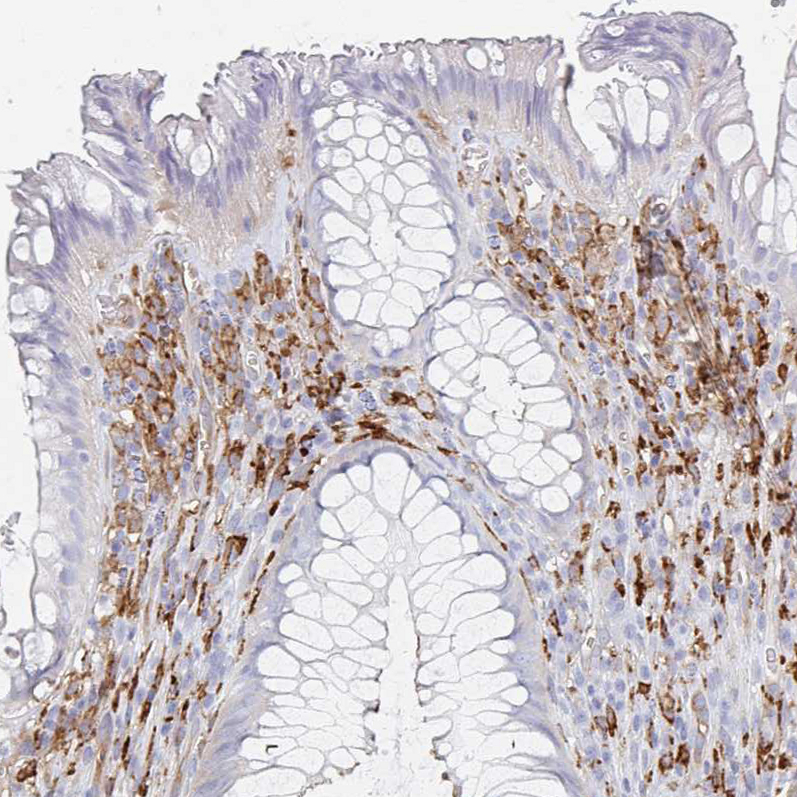

Immunohistochemistry analysis in human placenta and skeletal muscle tissues using HPA028888 antibody. Corresponding DAB2 RNA-seq data are presented for the same tissues.